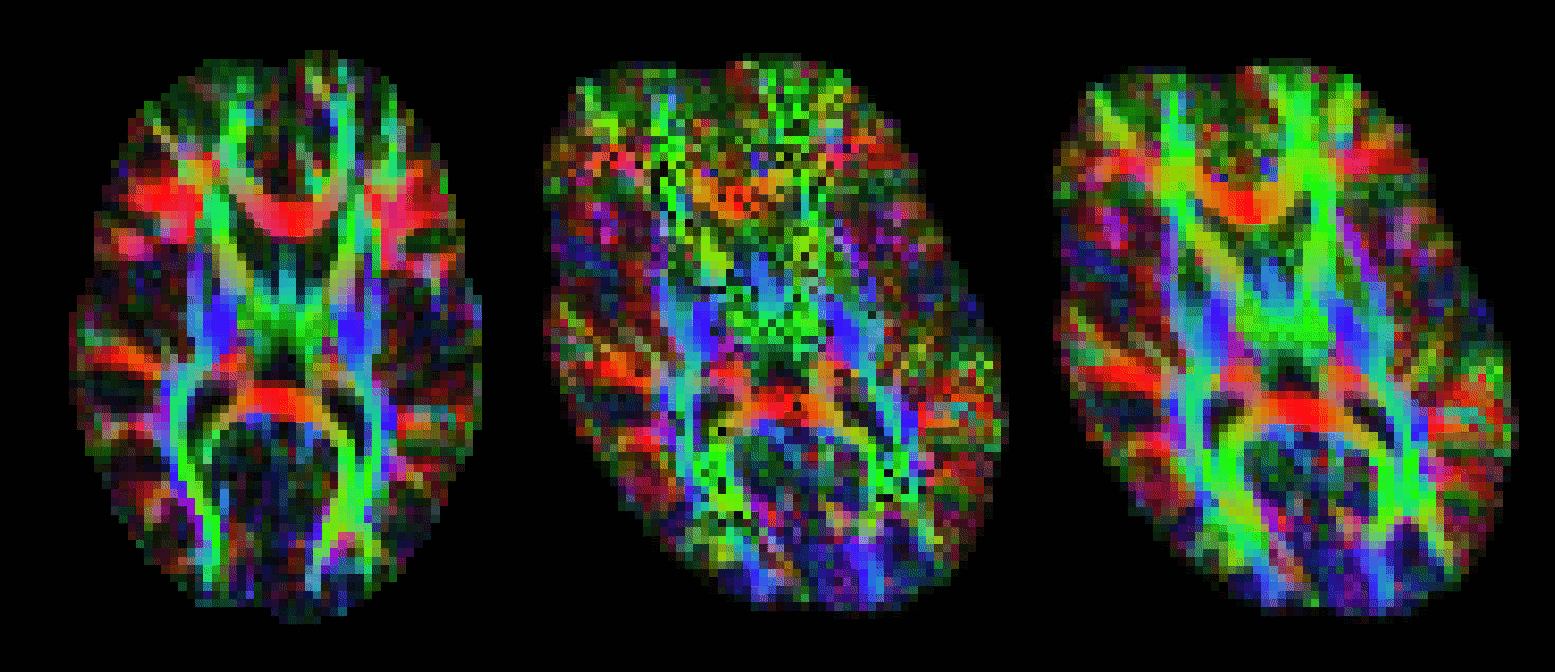

Outputs of bedpostx or dtifit can be conveniently displayed in fslview. If you open an image of diffusion vectors (e.g., dtifit_V1 output of dtifit or dyads<i> output of bedpostx) then it is possible to display these vectors using RGB coding (where the colours red,green and blue represent diffusion in the x,y,z axes respectively) or using lines where a line at each voxel represents the principle diffusion direction at that voxel.

It is also possible to display multiple lines per voxel. Each line will be displayed in a different colour. In the example above, the red lines represent the main fibre orientation, and the blue lines represent the secondary fibre orientations (thresholded at an f-value of 0.05), as calculated by bedpostx.